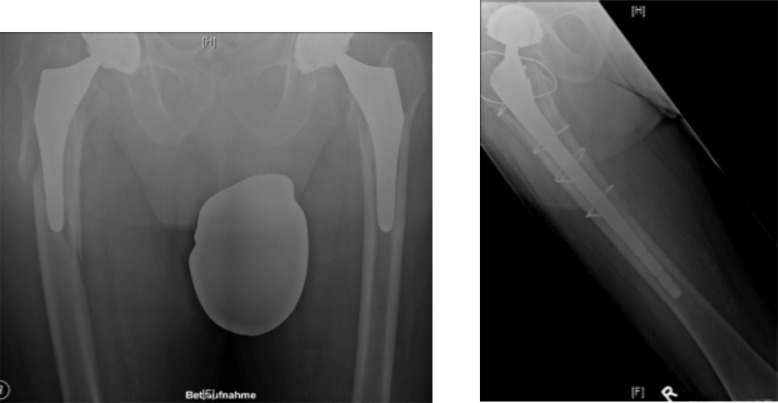

The idea of this concept is to achieve both centric drilling and longer anchoring distances, as well as maintenance of locking screw stability (Fig. 8).

Fig. (8).

X-Ray demonstration of intraprosthetic screw fixation [42].

Brand and coworkers demonstrated superior biomechanical properties for intraprosthetic screw anchorage compared to conventional monocortical locking screw fixation in both a Vancouver B1 fracture model with a cemented straight hip stem [42] and a Vancouver C fracture model [47]. This approach might represent a potential solution for osteosynthetic prodecures for patients with periprosthetic fractures with well-fixed implants, providing high primary stability and the potential of early full weight-bearing mobilization. Future clinical trials need to investigate this novel method.